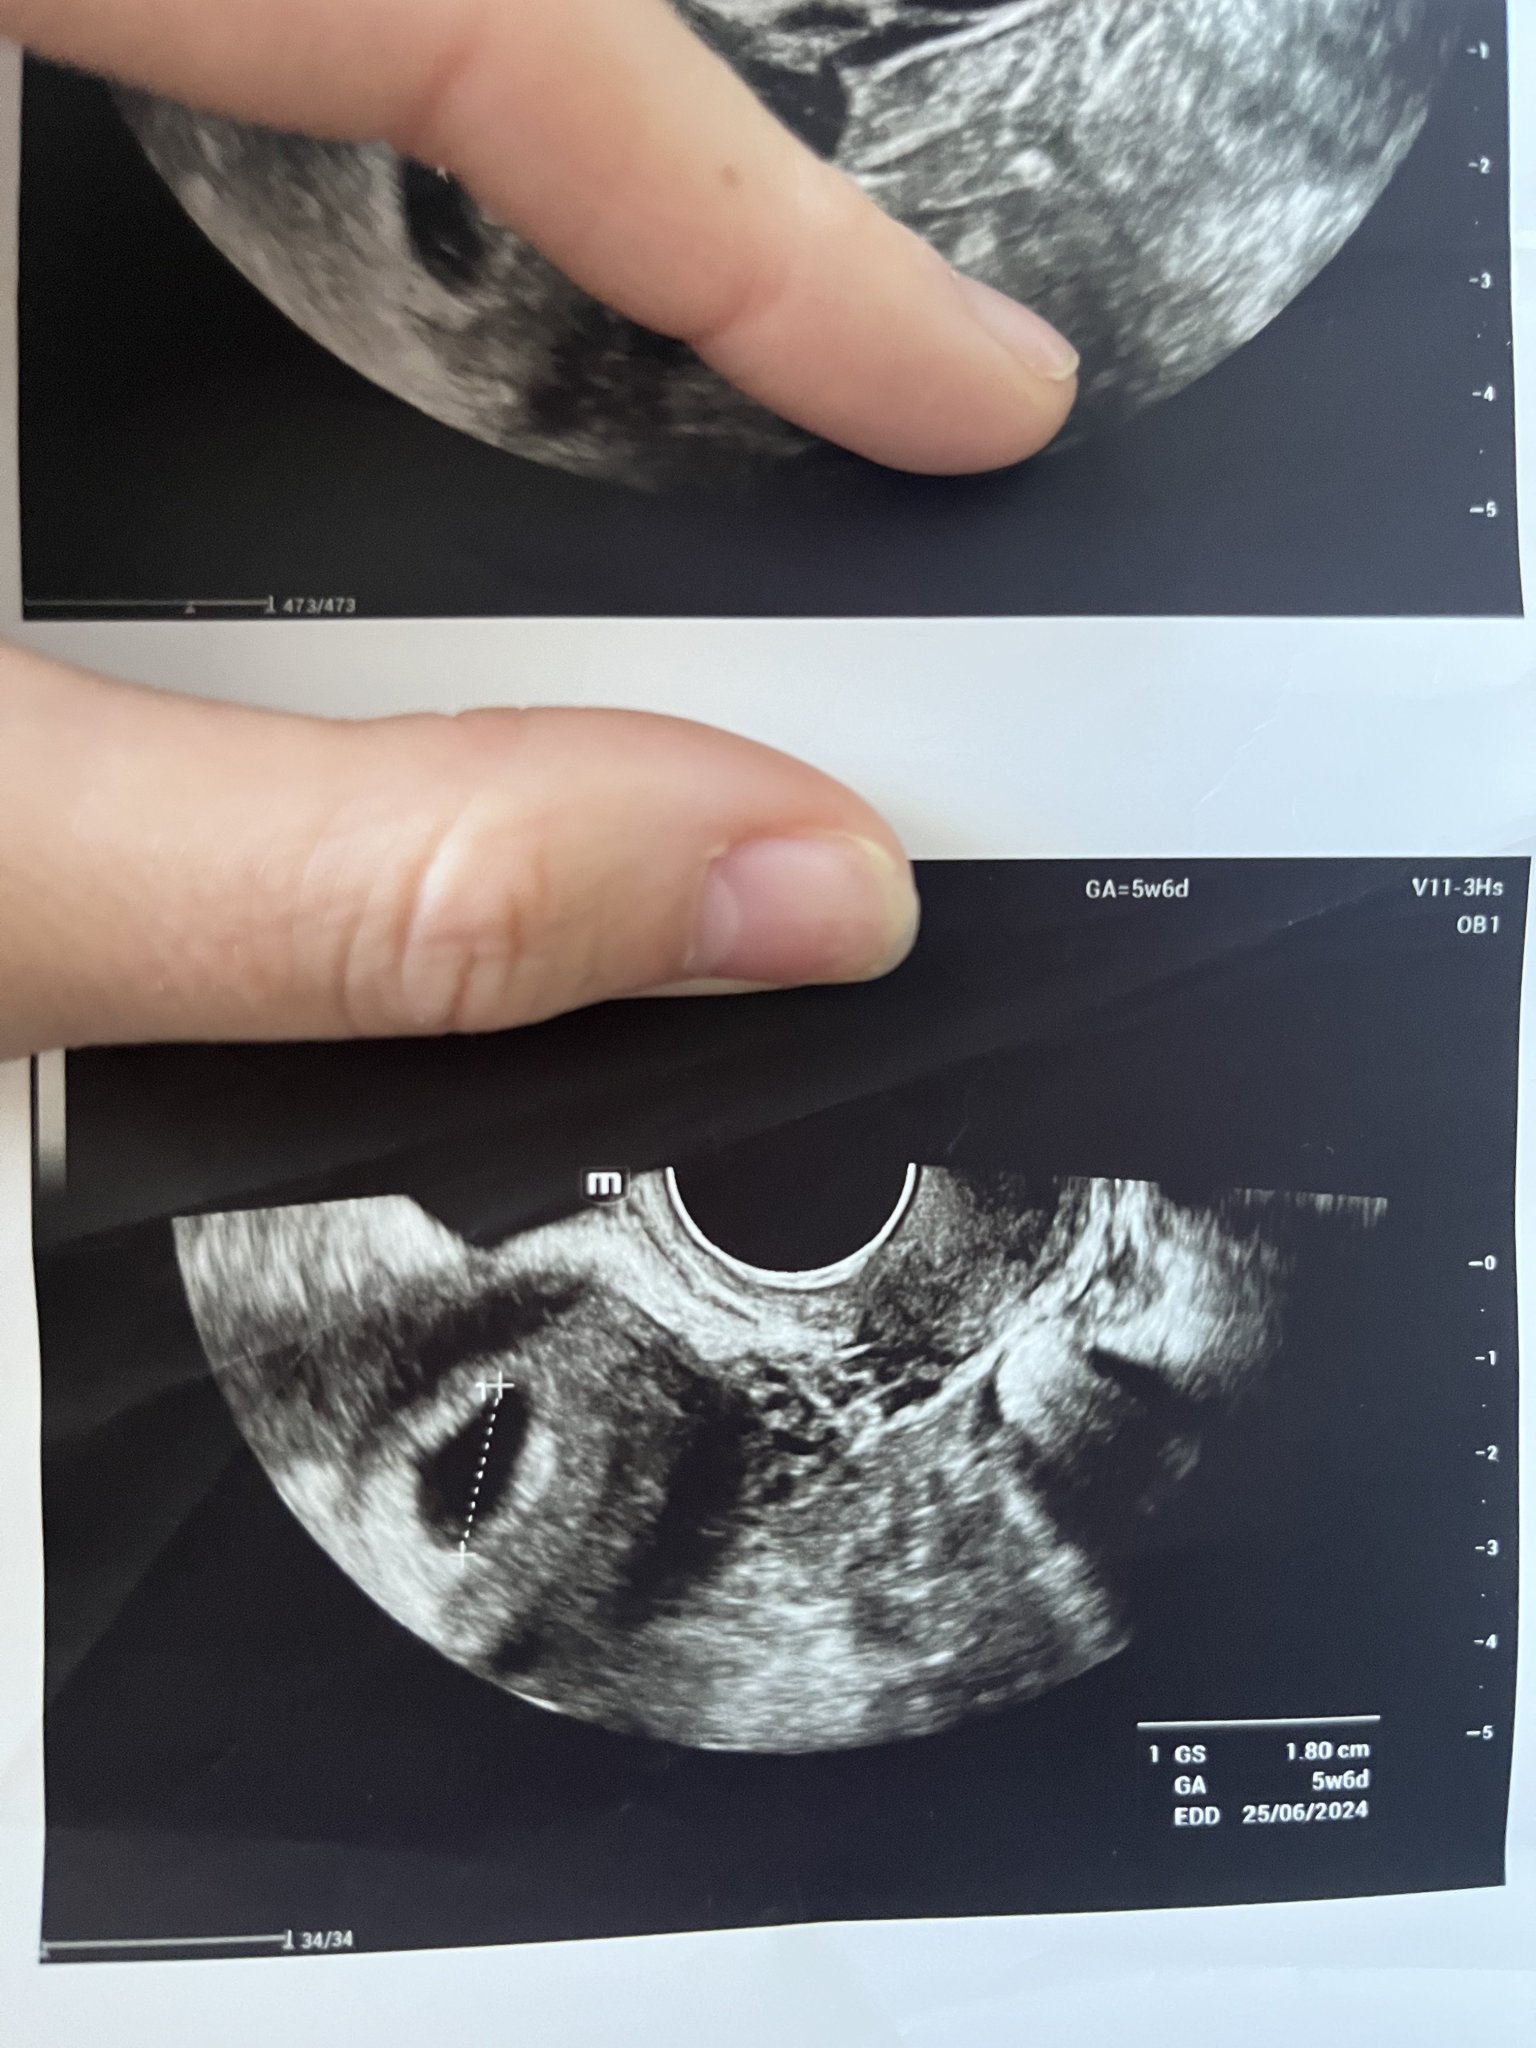

• Мнения: 16

Здравейте ! Първият ми ден от последната ми менструация беше на 20.09 ( като имам нередовен цикъл ).След няколко положителни теста , днес беше и първият ми преглед . Ще прикача снимки от него . Според лекаря съм имала късна овулация и съм още в самото начало на бременноста . Видя се правилно закрепено плодно сакче , с големина 4мм ( около 5 и 6 г.с), но без ембрион , защото е още много рано . След 2 седмици пак съм на преглед . Притеснява ме големината на плодния сак , не е ли малък ?